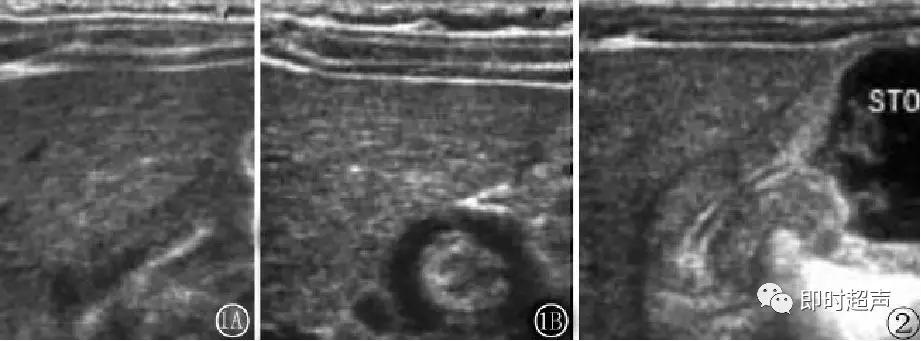

超声表现:

均质低回声团:“宫颈征”

肌层厚 >4mm (正常<3mm)

幽门直径 >14mm

幽门管长 >16mm(正常<15mm )

管壁蠕动消失

胃腔扩张

幽门肥厚狭窄声像图:

增厚的幽门肌层(三角箭头之间),增长的幽门管(长箭头之间)。

先天性肥厚性幽门狭窄

幽门纵切呈“宫颈征”。幽门横切面呈“靶环征”

幽门环形肌纵向呈低回声圆柱体

幽门环形肌“同心圆”征